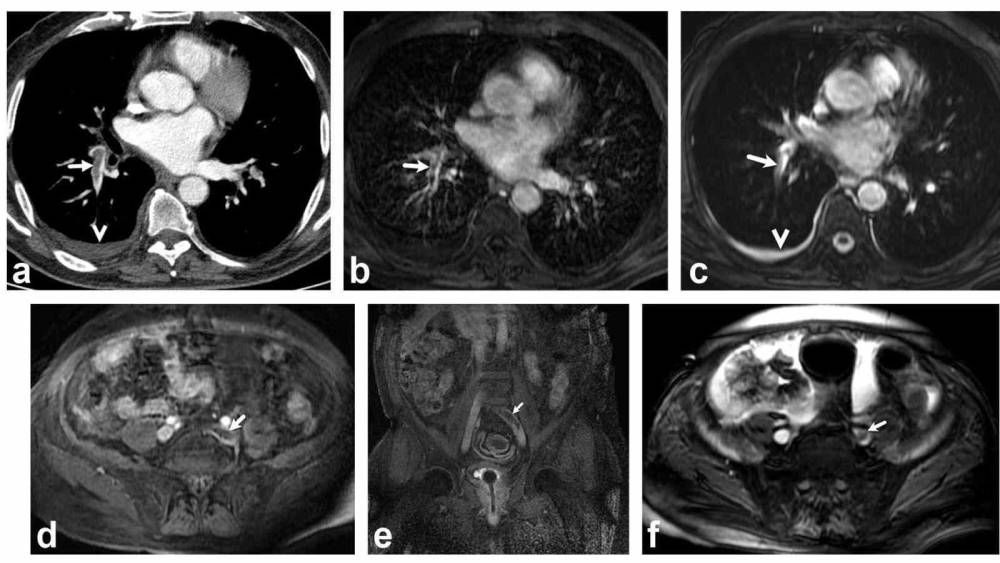

Bir dönem Denizli Tekden Hastanesinde de çalışan ve çalışmalarına ABD’de devam Dr. Nevzat Karabulut ve ekibinin yaptığı, British Journal of Radiology dergisinde yayımlanan "Diagnostic performance of contrast-enhanced and unenhanced combined pulmonary artery MRI and magnetic resonance venography techniques in the diagnosis of venous thromboembolism" başlıklı araştırmada manyetik rezonans (MR) yöntemi kullanılarak hem akciğer damarlarının hem de pıhtının kaynağı olan bacak toplardamarlarının aynı anda, tek bir incelemede değerlendirilebileceği gösterildi. Toplam 44 hastanın incelendiği çalışmada elde edilen sonuçlar oldukça dikkat çekti.

Kontrastlı MR yöntemi, hastaların tamamında akciğer embolisini doğru şekilde tespit ederken; kontrastsız MR yöntemi de yüksek doğruluk oranına ulaştı ve önemli ölçüde güvenilir sonuçlar verdi. Bu bulgular, radyasyon içermeyen MR yönteminin pıhtı hastalığını saptamada güçlü bir alternatif olduğunu ortaya koydu. Özellikle Radyasyon riskinin daha önemli olduğugenç hastalarda ve gebelerde MR’ın güvenli ve etkili bir seçenek olabileceği vurgulandı.